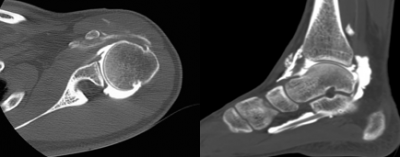

Arthroscanner

On utilise un contraste opaque iodé hydro-soluble non ionique. Lorsque l'arthroscanner poursuit une arthrographie et que cet arthroscanner a été prévu. On peut réaliser l'arthroscanner 1/2 heure à 1 heure après l'injection de l'arthrographie. un contraste opaque iodé hydro-soluble non ionique. Lorsque l'arthroscanner poursuit une arthrographie et que cet arthroscanner a été prévu. On peut réaliser l'arthroscanner 1/2 heure à 1 heure après l'injection de l'arthrographie.